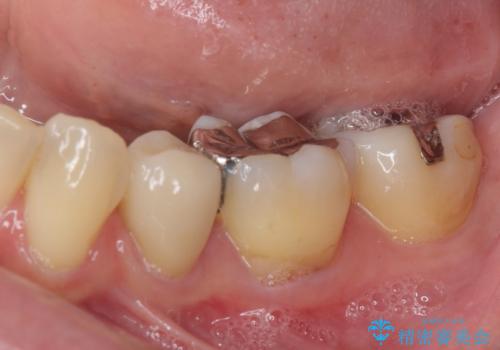

矯正治療後には、下顎臼歯の目立つ銀歯をセラミックインレーにて修復治療を行いました。

口を開けたときに金属が見えなくなり、患者様には大変満足していただきました。